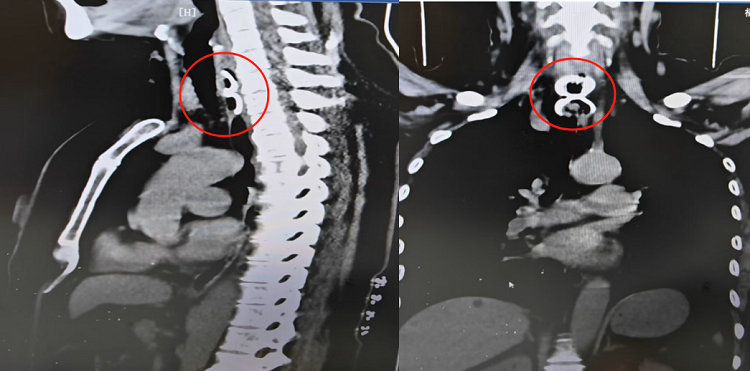

我院耳鼻咽喉科林清花主治醫(yī)師迅速檢查咽部、喉部均未發(fā)現(xiàn)異物后,立即安排患者行胸部CT檢查,提示食管上段見(jiàn)條片狀致密影,長(zhǎng)約3.5cm。